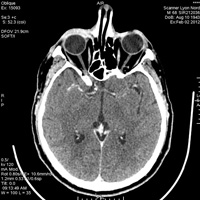

C’est vrai que c’est pas évident du tout mais en général les os beaucoup plus blanc au scanner que sur IRM

- 4938037C-4F15-4C32-BC26-82DB79A7839B.jpeg (17.46 Kio) Vu 238 fois

= scanner